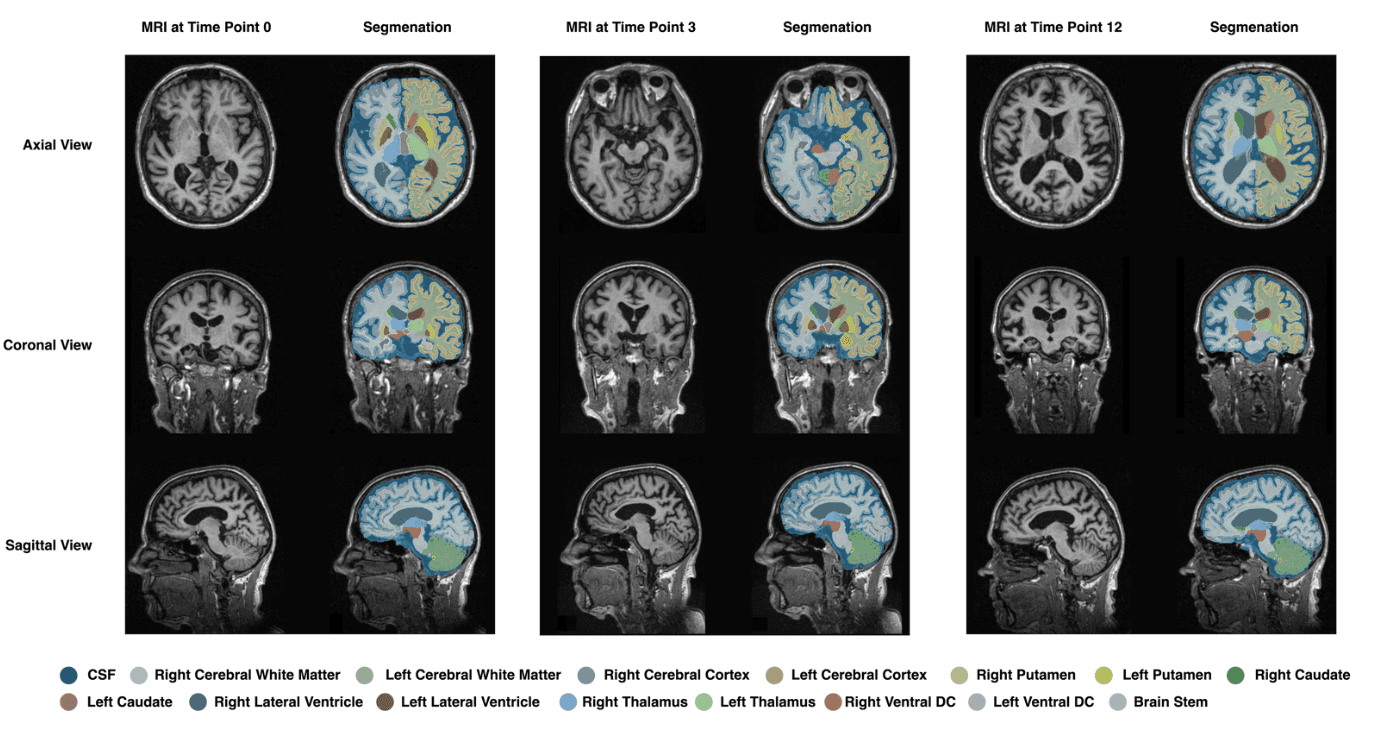

The dataset consists of MRI scans, genomic data, and clinical assessments. The ANMerge dataset, containing data from 1,702 participants, is used in this study. The data includes four classes: AD, VaD, Mild Cognitive Impairment (MCI), and Control (CTL). Longitudinal MRI scans are segmented using the SynthSeg tool to extract radiomics features from 32 brain structures.

2. MRI Feature Extraction

Using PyRadiomics, 137 radiomics features are extracted from each of the 32 segmented brain structures. These features capture shape, texture, and voxel-level tissue patterns critical for distinguishing AD and VaD.